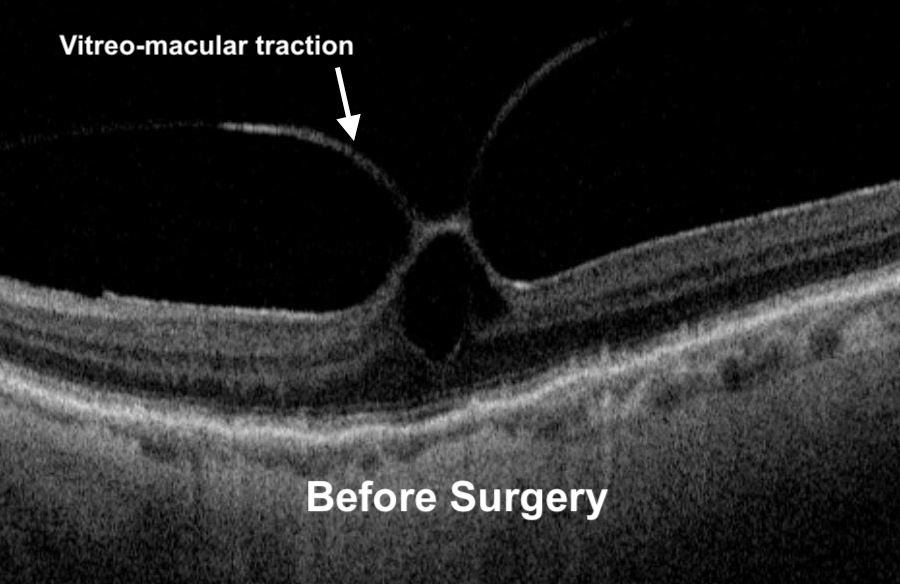

Vitreomacular Traction I Mr Ellabban Eye Surgery Yorkshire & Hull Laser Eye Surgery Yorkshire Clinic With over 20 years of experience in eye surgery, he now leads. the three main types of laser eye surgery are lasik, lasek and relex smile. A laser creates a flap which. Laser eye surgery, cataract surgery and lens replacement are easily accessible from our yorkshire eye hospital. Lasik is the most popular type of laser eye surgery. . Laser Eye Surgery Yorkshire Clinic.